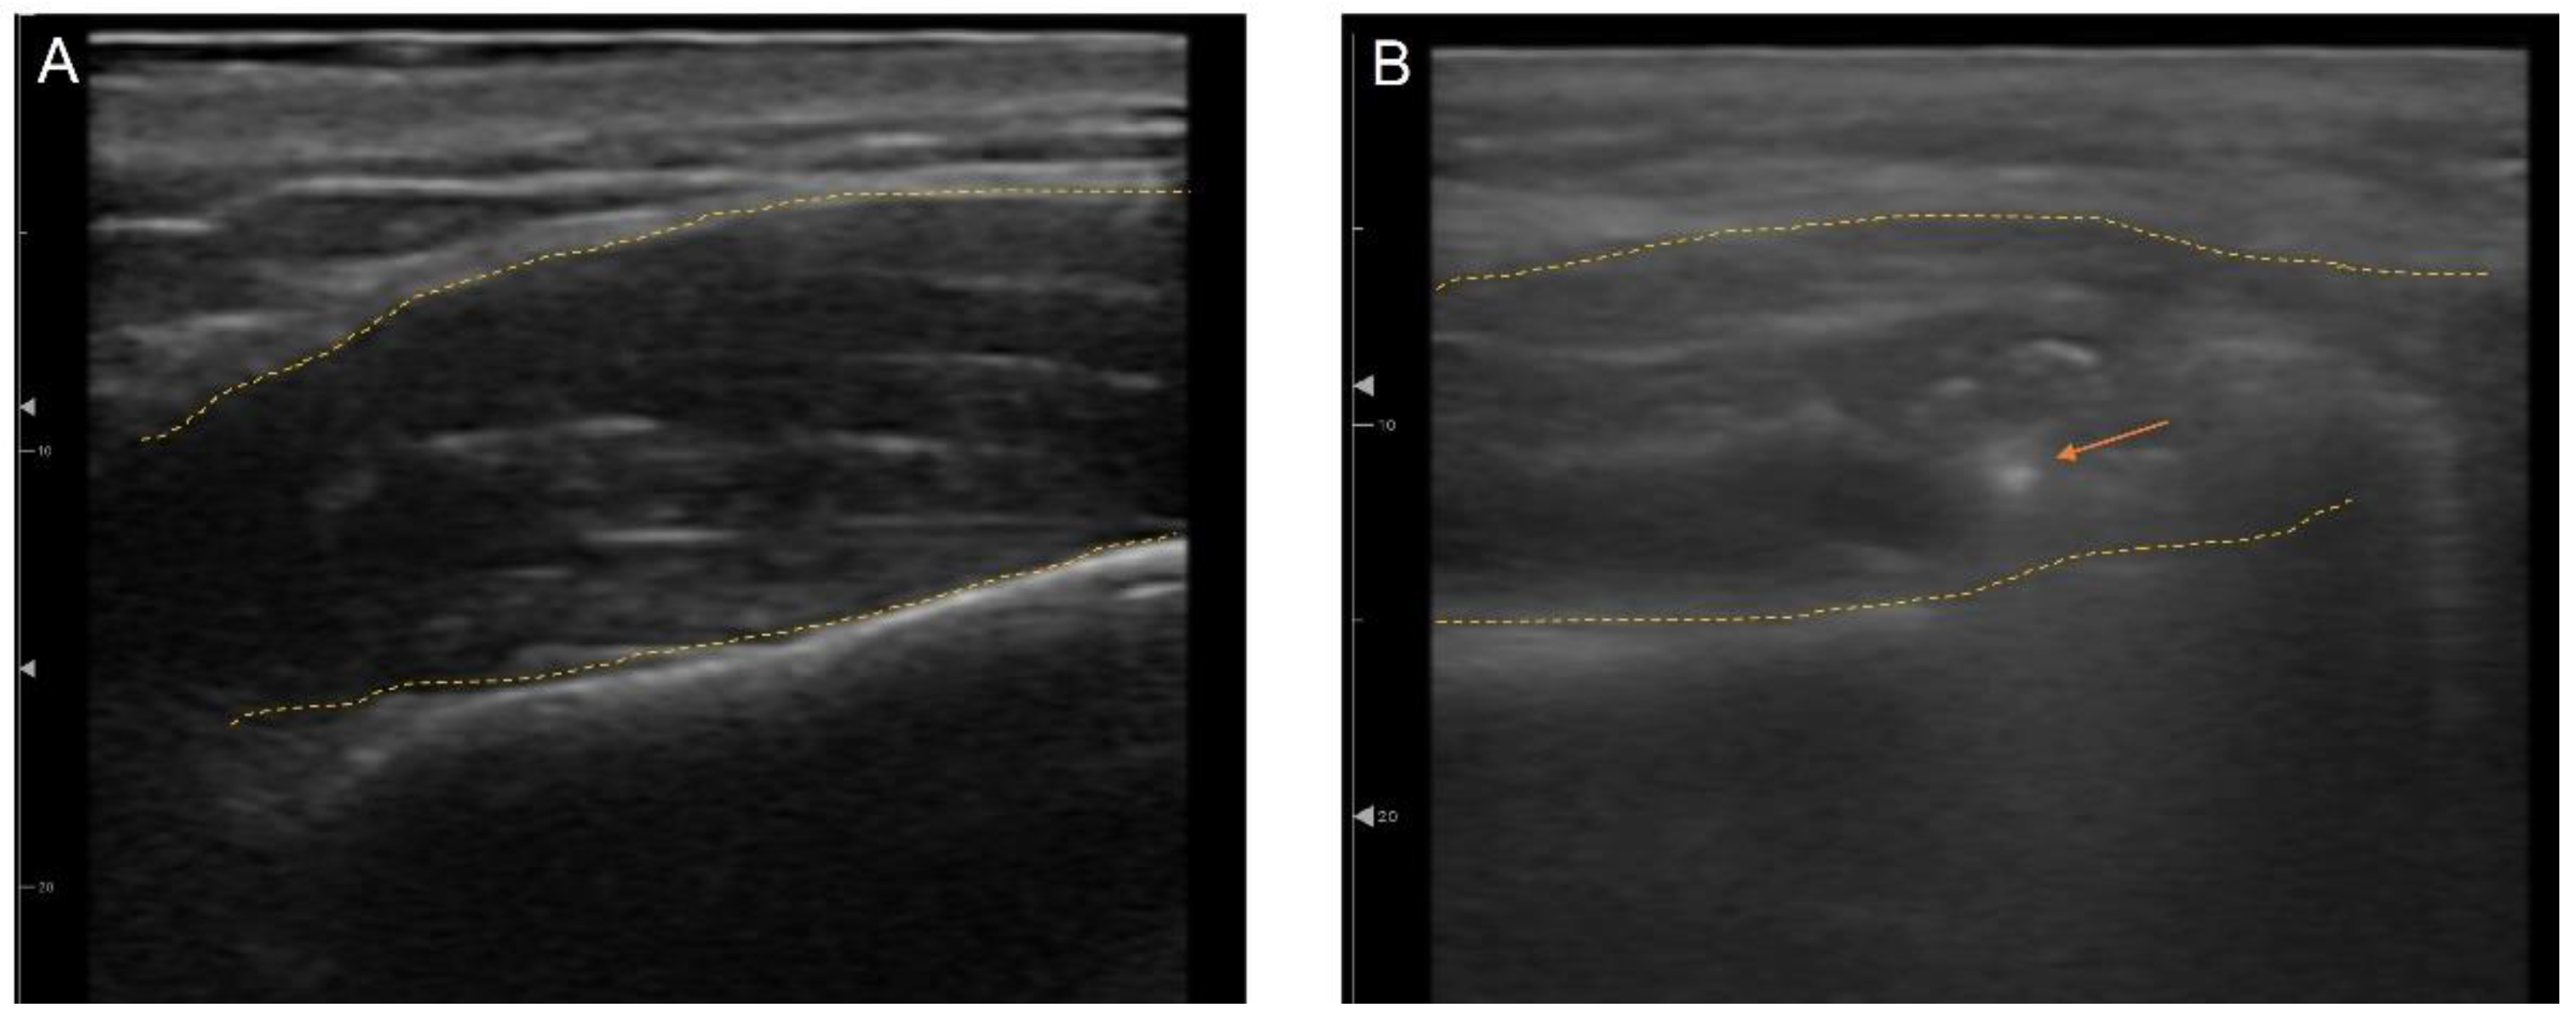

To maximize accuracy and minimize complications, US-guided treatments have been actively utilized in minimally invasive esthetic treatments, such as BoNT, fillers, and threads [65,78,79]. US is useful for distinguishing between anatomical structures such as vessels, muscle, fat, bone, and glands [66]. Not only can anatomical landmarks be seen in real time, but also injection needles and cannulas can be visualized during the procedures, which make outcomes more predictable (Figure 12). Therapy can be reproducible, which increases the efficacy and safety of esthetic treatments. Rather than injecting blindly into a muscle or layer, BoNT can accurately target a selected area and thereby treat the asymmetry in patients with crooked smiles or even deviated lower faces [80,81].

Figure 12.

Ultrasonography imaging with outline of the muscle (yellow dotted line) (A) masseter, (B) masseter with needle tip (orange arrow).